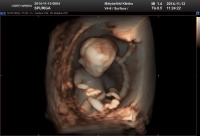

Szia, ez milyen ultrahang? már 5Ds? nagyon jól látszik rajta minden. :)

spurigambrigi. nagyon aranyos milyen kép ez? ilyet még nem láttam.

5D-s uh-n voltam. De hogy ez már 5D kép??? Foggalmam sincs :lol: én még 3 meg 4D-set sem láttam. De.mindenki csodálkozik, hogy még csak 67 mm, hogy nagyobbnak látszik...

Brigi:) döbbenetes ez az uh kép......nagyon cuki:)

Sziasztok! Brigi szuper ez az uh kép!!hol csináltattad?? én is ilyet akarok!Gyönyörű a babád, már most olyan mint egy kész gyerek:)és még csak 13 hetes..hihetetlen!

A Mátyásföldi klinikán voltam, 20 e volt az uh, nem voltam benne biztos, hogy nem-e lett volna elég máshova menni, ahol olcsóbb... De olyan kedvesek voltak, és mindent tényleg megnéztek alaposan, és eddig még nem is láttam ilyen jó uh képeket a babámról, hogy végül nem bántam meg, és a 18. hetire is oda megyek :-D

Brigi mit jósolnak, kisfiú vagy kislány????ezeken a szupi képeken már vannak apró jelek nem????

Még nem mondtak semmit, illetve, nem tudom, hogy ez már utalás volt-e, de annyit mondott az ultrahangos, h ilyenkor még nem tudja megmondani, hogy egy megduzzadt csiklót lát vagy fütyit... :-P annyira nem látok bele ebbe a mondatba semmit (talán csak azért, m én csajszira pályázók 8-) ).